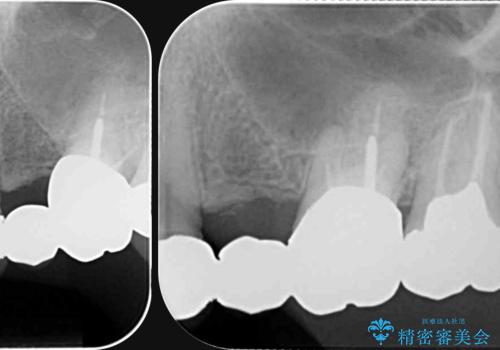

- 長年使用し、見た目の気になってきた金属製のブリッジのやりかえを希望され来院されました。

老朽化した金属製のブリッジを丁寧に除去したのち、金属を用いない審美性の高いセラミック製のブリッジでのやりかえを計画します。